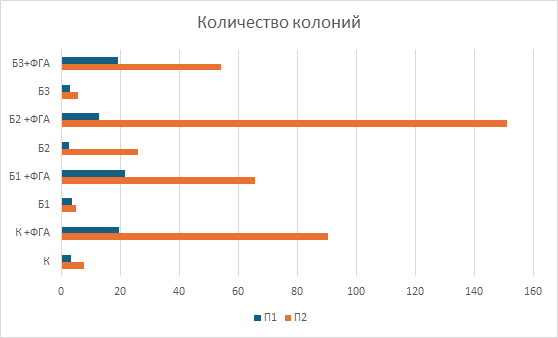

При исследовании чувствительности мононуклеарных клеток периферической крови к берберинуin vitroбыло выявлено стимулирующее влияние берберина на их пролиферативную способность, проявлявшееся увеличением количества и площади формируемых колоний. При этом благоприятный клинический исход ассоциировался не с более высокой базальной колониеобразующей активностью, а с формированием более крупных колоний, что может отражать наличие лимфоцитарных клонов с более высоким пролиферативным и метаболическим потенциалом. Это позволяет предположить, что прогностическое значение может иметь не общее число клеток, а качественные характеристики клонального пролиферативного ответа (рис.3, 4).

У пациента с благоприятным клиническим ответом изначально отмечалась более низкая базальная колониеобразующая активность МНПК: количество колоний было на 56% меньше по сравнению с пациентом с рефрактерным течением заболевания, однако их средняя площадь превышала данный показатель на 22%. Воздействие берберина в исследованных концентрациях вызывало дозозависимое усиление колониеобразующей способности МНПК у обоих пациентов, при этом наибольшая стимуляция наблюдалась при сочетанном применении берберина и фитогемагглютинина, что свидетельствует о синергическом эффекте изучаемого соединения с митогенной стимуляцией (рис.5, 6). Использование ФГА позволило оценить влияние берберина в условиях активированной иммунной реакции, что приближаетмодель in vitro к условиям реализации противоопухолевого иммунного ответаin vivo.

Кроме того, были выявлены индивидуальные различия в чувствительности МНПК к берберину: у пациента с полным ответом на терапию наибольшее увеличение количества колоний наблюдалось при концентрации 1мкмоль/л, тогда как у пациента с неблагоприятным исходом пик пролиферативного ответа смещался на 2мкмоль/л (рис.5). Полученные различия могут объясняться особенностями метаболической и пролиферативной активности отдельных лимфоцитарных клонов. Более крупные колонии у пациента с благоприятным исходом могут отражать наличие клонов с высоким метаболическим потенциалом и способностью к интенсивному клеточному делению, тогда как большее число, но мелких колоний у пациента с неблагоприятным исходом может соответствовать функционально менее активным клональным линиям.

Рис.5. Количество образовавшихся колоний мононуклеарных клеток периферической крови при добавлении различных концентраций берберина. К – контроль, К + ФГА – контроль + ФГА, Б1 – берберин 1мкмоль, Б1 + ФГА – берберин 1мкмоль + ФГА, Б2 – берберин 2мкмоль, Б2 + ФГА – берберин 2мкмоль + ФГА, Б3 – берберин 4мкмоль, Б3 + ФГА – берберин 4мкмоль + ФГА.

Примечание: составлен авторами по результатам данного исследования